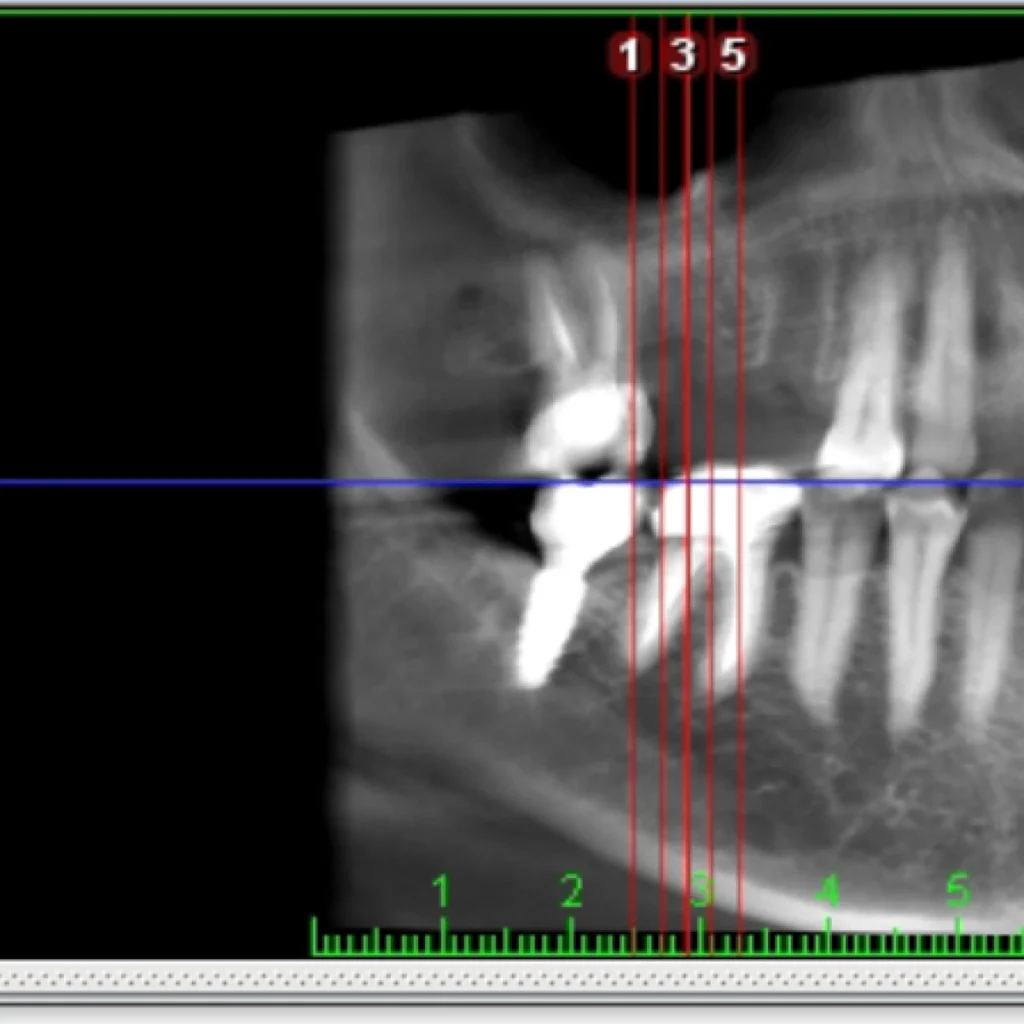

Un cone beam (équivalent d’un scanner) est réalisé sur place afin de valider le diagnostique et de vous proposer le traitement adapté à votre situation. Certaines font intervenir des biomatériaux (os de banque d’origine humaine ou animale; os de synthèse; os autogène prélevé directement dans votre bouche lors de l’intervention).

- Le scanner réalisé au cabinet met en évidence un défaut osseux majeur nécessitant une greffe osseuse complexe pour réhabiliter la zone par 2 implants.